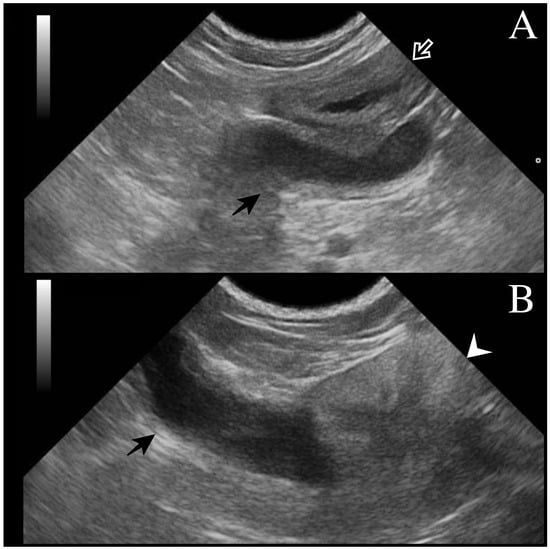

All dogs underwent a complete assessment supplemented with laboratory and ultrasonographic abdominal examination. At presentation, case 1 was asymptomatic, and the tubular fluid-filled structure in the scrotum was detected occasionally by the referring veterinarian during a routine consultation. Cases 2 and 3 presented clinical signs compatible with systemic infection (fever, depression, disorexia/anorexia, vomiting) as described in bitches during pyometra. Except for case 1 (no alterations detected), neutrophilic leukocytosis was observed from the hematological and serum chemistry profiles. In all cases, ultrasound examination revealed a tubular fluid-filled structure with a thin irregular wall located cranially to the prostate and in continuity with the cranial part of the gland (Figure 1). In cases 1 and 2, two other tubular fluid-filled structures were visualized in the caudal part of the abdominal cavity, ventrally to the prostate gland and urinary bladder. In case 3, prostatic metaplasia and preputial keratinization were indicative of hyperestrogenism. Explorative laparotomy was carried out in all dogs, and a bi-horned structure with a stalk connected to the dorso-cranial portion of the prostate gland was recognized. The structure extended caudally in the abdominal cavity engaging in the deep inguinal ring on each side; complete resection was performed in all cases, and in cases 1 and 3, the surgery was completed with orchiectomy. Macroscopically, the bi-horned structure was similar to a fluid-filled female uterus (Figure 2). Table 1 illustrates a comparison of clinical data from the three cases, including anamnestic and clinical details.

Figure 1. Transverse ultrasonographic image of uterus masculinus: (A) Black arrow points to the uterus masculinus filled with hypoechoic fluid and localized near the urinary bladder (white arrow). The wall of the uterus masculinus is isoechoic to the urinary bladder wall. (B) Uterus masculinus with a fluid-filled lumen (black arrow) originating from the cranial part of the prostate gland (white arrowhead) and extending cranially.